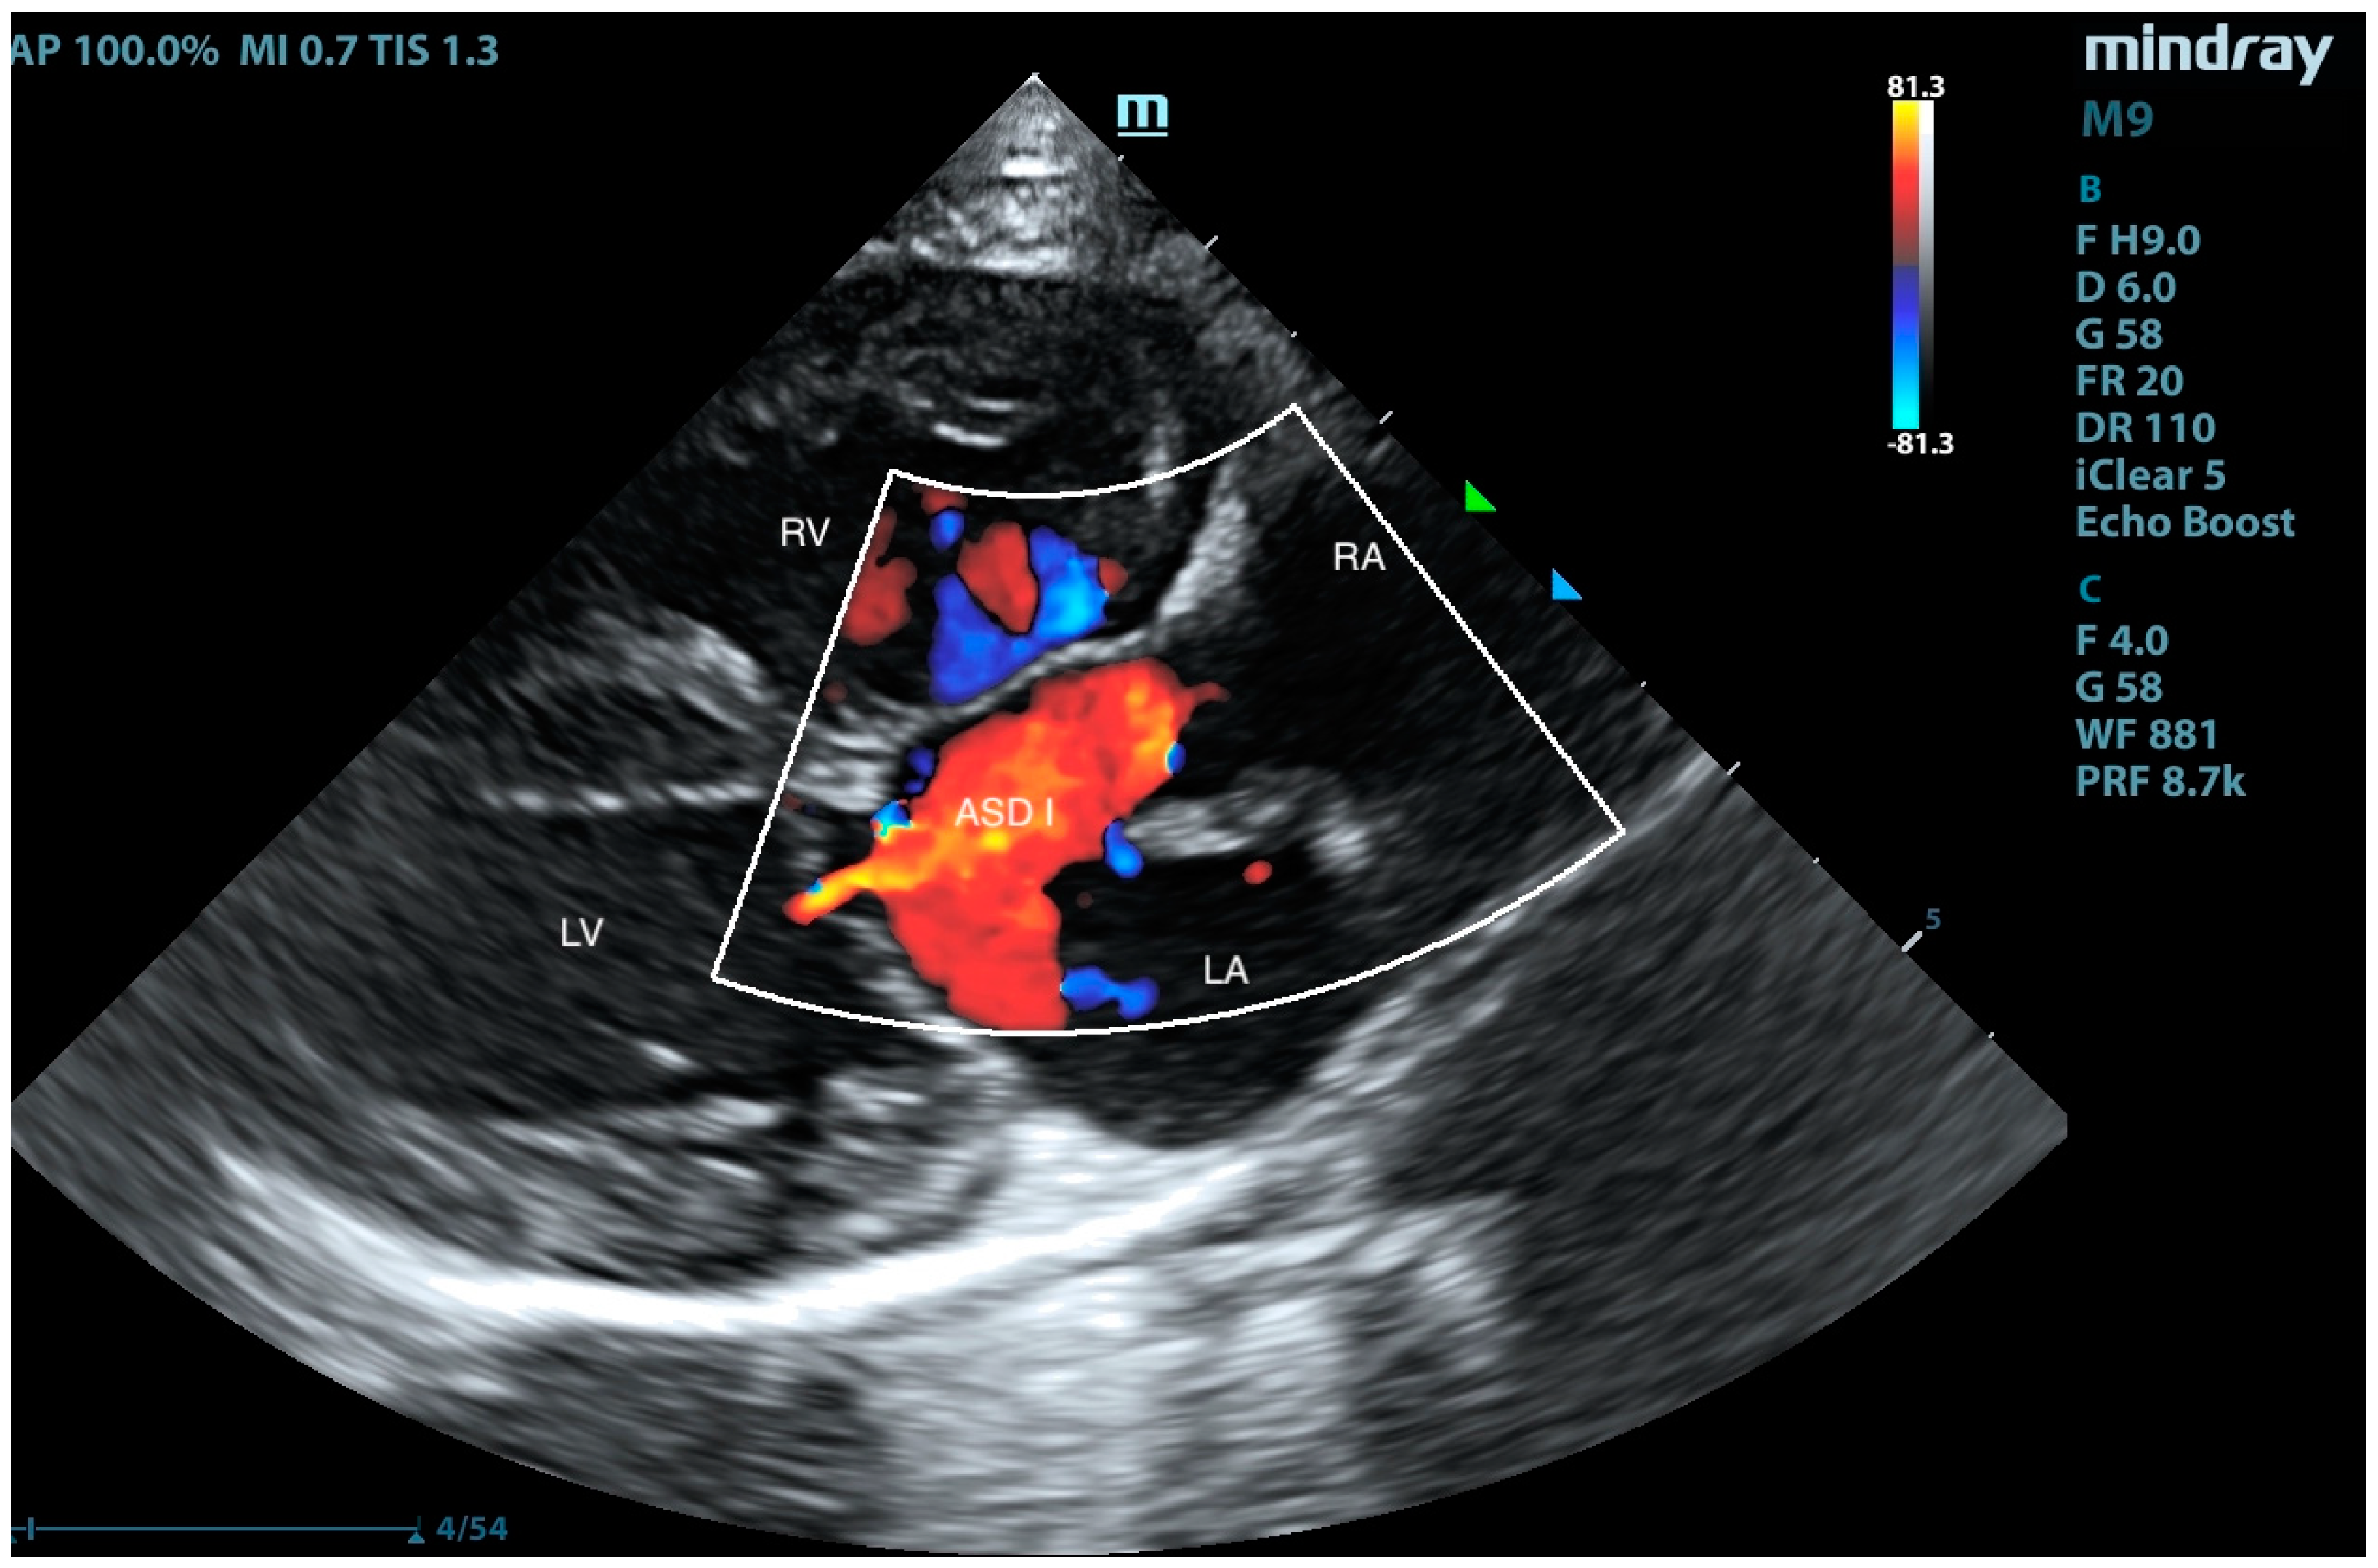

2. Case Presentation